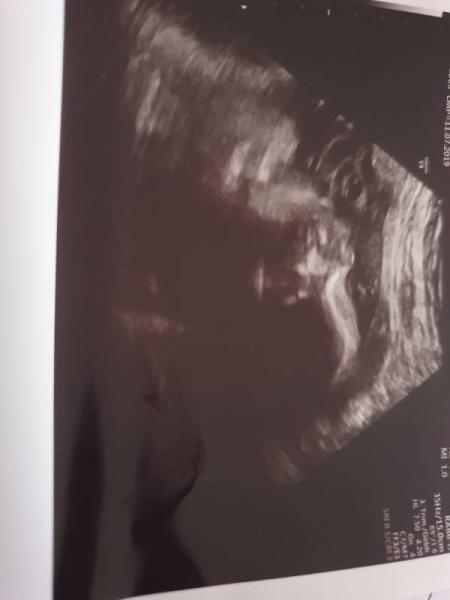

Heute 28+5 und dem Zwerg geht es super . Er hat sich in Schädellage gedreht und somit bereit für den Start . Er wiegt ca 1150 Gramm und is knapp 37 cm. Mein Arzt sagte es wird ein zierliches Baby,der Bauch is etwas zierlich aber ansonsten gut entwickelt, Herz und Hirn macht was es soll. Mein HB ist auf 8.0 unter 7.5 verschreibt er mir was hier wird er in mmol/l abgenommen somit bis jetzt im grünen Bereich. Darf jetzt alle 2 Wochen,und in 4 Wochen hab ich da erste mal CTG. Er hat beim US grad "getrunken" Mund auf Mund zu . Leider hat ein 3 d Foto wieder nicht geklappt -.-

Bild zu Zurück vom Frauenarzt - Forum für April - Mamis